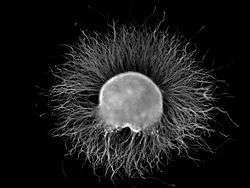

In anatomy, a ganglion (/ˈɡæŋɡliən/ GANG-glee-ən; plural ganglia) is a nerve cell cluster[1] or a group of nerve cell bodies located in the autonomic nervous system.[2][3] Ganglia house the cell bodies of afferent nerves.

In a neurological context, ganglia are composed mainly of somata and dendritic structures which are bundled or connected. Ganglia often interconnect with other ganglia to form a complex system of ganglia known as a plexus. Ganglia provide relay points and intermediary connections between different neurological structures in the body, such as the peripheral and central nervous systems.